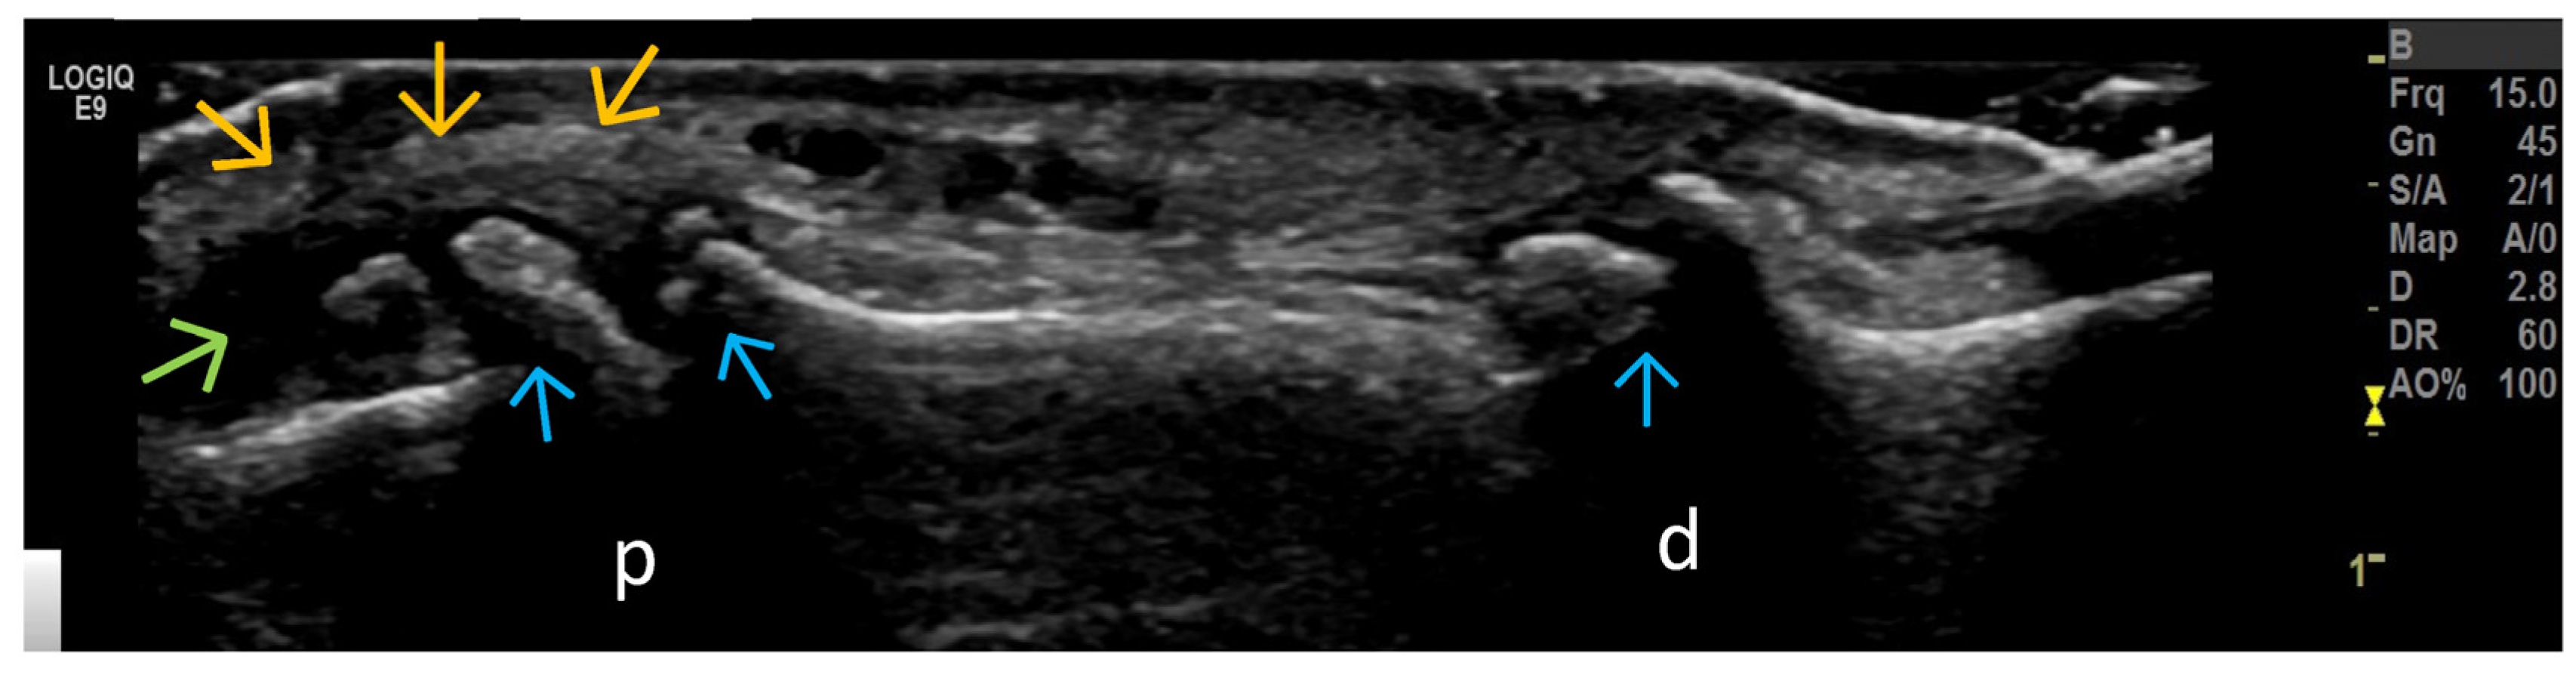

4. Examples of US Phenotypes